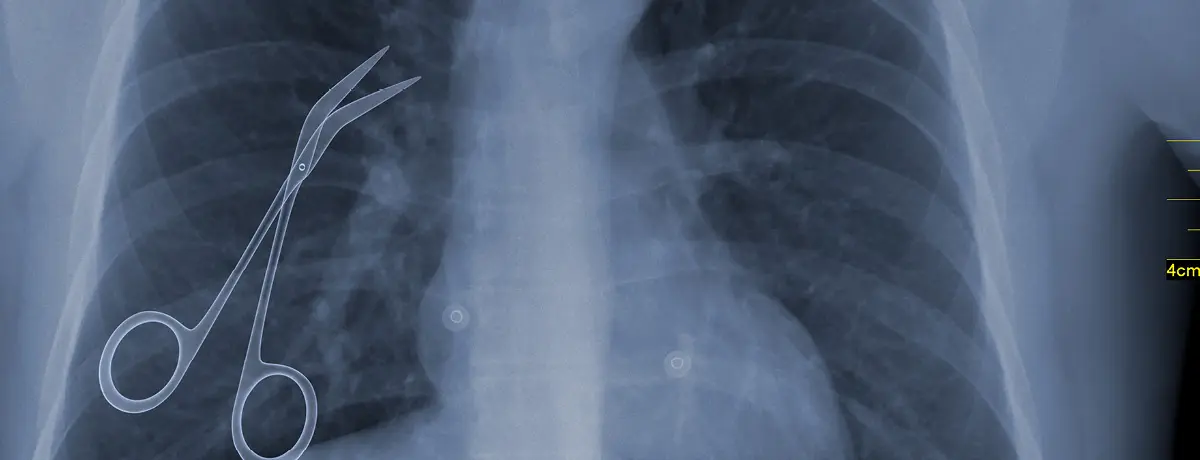

X-ray image of a patient's chest showing surgical scissors inadvertently

• Surgical Errors: Examples include operating on the wrong site, leaving instruments inside a patient or failing to monitor vital signs. Surgical errors often stem from lapses in communication or protocol.

Headline Image: Adobe Stock/Jose Luis Stephens